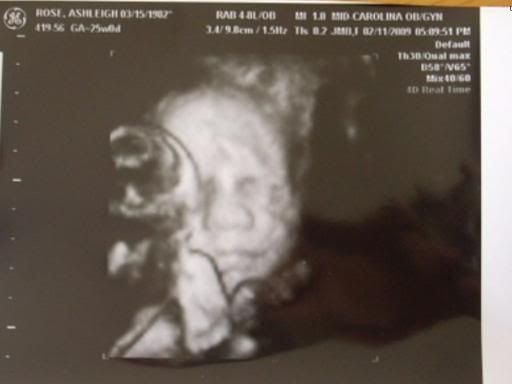

One of my baby girls. The other baby had her face down, so we couldn't get a good picture of her face. There is a foot right in front this baby's chin if you look carefully, and a butt in front of her right eye. They still have a lot of plumping up to do in the next 10-14 weeks, but I just thought she was already so pretty.